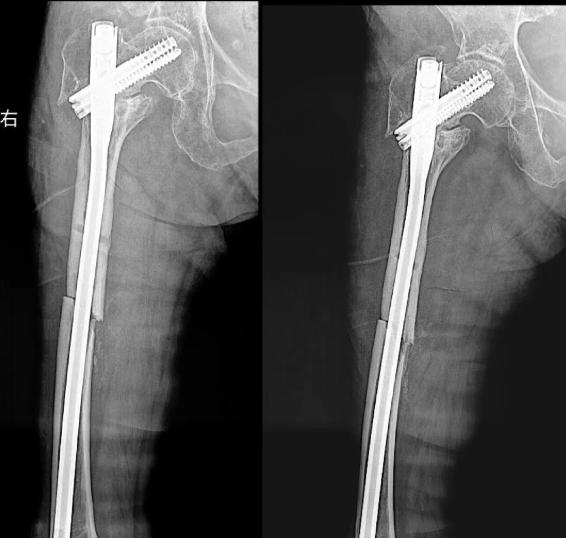

术前

术后

患者化奶奶年近八旬,十二年前因右股骨转子间骨折术后始终未能脱离拐杖,行走困难。近日不慎摔倒导致右侧股骨干再次骨折,且与旧内固定物相互交织,病情极为复杂棘手。面对这一高难度挑战,周口人合医院骨三科在孙杰院长的亲自带领下,迅速启动多学科会诊机制,精准制定了“微创取出原内固定+同期髓内钉复位固定”的一体化手术方案。

手术由骨三科团队精心实施,以微创为核心,在精准操作下巧妙处理了新旧伤情,极大降低了手术创伤。术后,科室医护团队全程精细管理,结合系统化、个性化的康复方案,循序渐进指导功能锻炼。在医疗技术与人文关怀的双重护航下,化奶奶的骨折顺利愈合,肢体功能得到显著恢复,最终成功放下了依赖十二年的拐杖,实现了独立行走的夙愿。